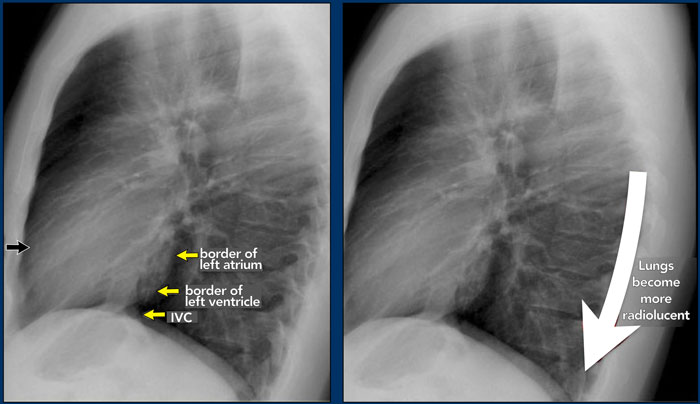

Lateral view

On a lateral chest radiograph, the cardiac borders should be well defined, and the inferior vena cava (IVC) can typically be seen entering the right atrium.

Retrosternal Clear Space

The retrosternal space normally contains aerated lung and should therefore appear radiolucent (dark on the radiograph), extending inferiorly to the level where the right ventricle contacts the sternum (small black arrow).

Any radiopacity within the upper retrosternal space is suspicious for a lesion in the anterior mediastinum or a mass arising from the upper lobes of the lungs.

Spine Sign

When evaluating the vertebral bodies on the lateral view, they should appear progressively more radiolucent (darker) from top to bottom due to the increasing amount of aerated lung overlying them (white arrow).

If the lower thoracic vertebrae appear abnormally dense, it may indicate pathology in the lower lobes, such as consolidation or mass lesions — this is known as the spine sign.

Diaphragm Evaluation

• The right hemidiaphragm should be clearly visible anteriorly up to the chest wall (red arrow), representing the interface between aerated lung and abdominal soft tissues.

• The left hemidiaphragm is usually visible only up to the point where it is adjacent to the cardiac silhouette (blue arrow), beyond which the interface is lost due to the similar radiodensity of the heart and upper abdominal contents.